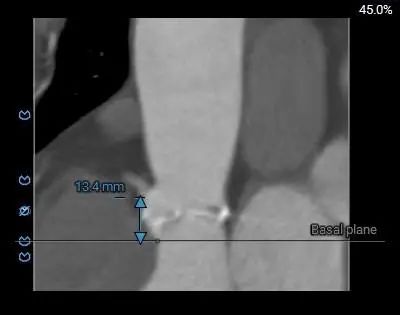

术前CT评估

主动脉根部测量

三叶式主动脉瓣,中重度钙化并增厚,水平夹角45°;LVOT敞口